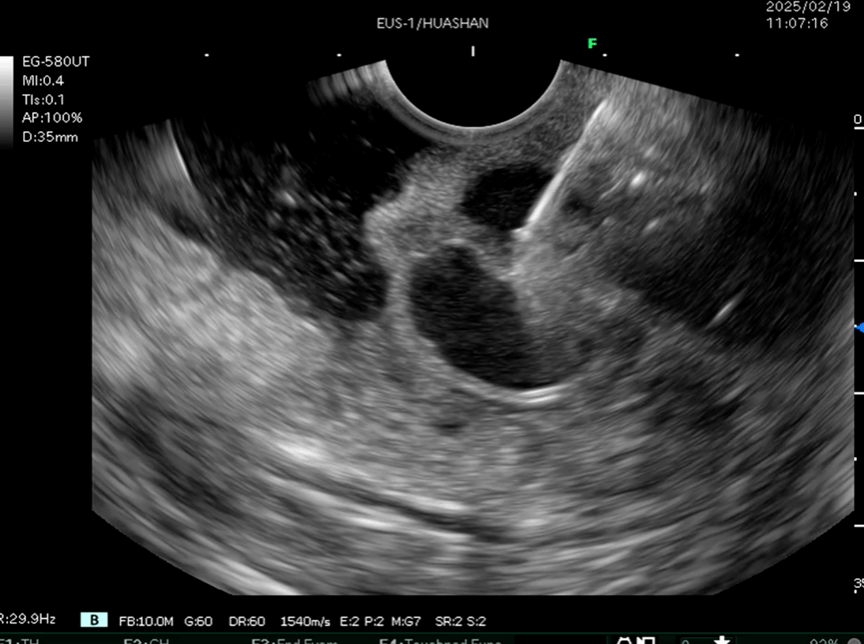

本次手术由消化内科史海涛副主任、马师洋副教授、赵菊辉副教授及袁佳医师组成核心术者团队,依托超声内镜系统,创新性采用"弹簧圈骨架支撑+组织胶生物封堵"双联疗法。术中使用多普勒超声实时导航技术,精确定位大小为3×2.5cm的曲张静脉团块。通过预载式FNA穿刺系统,将医用级钛合金弹簧圈精准植入曲张血管腔道形成物理支撑,继而注入医用组织胶与聚桂醇复合制剂,在血管腔内形成稳定的生物-机械复合栓塞体。与传统内镜治疗方法相比,该术式具有显著优势。一方面,能够借助超声多普勒实时评估血流动力学变化,实时监测手术进程,最大程度规避误穿风险;另一方面,持久的栓塞效果有效降低了再出血率,同时巧妙地规避了异位栓塞风险,极大减少了术中出血风险,为患者的生命安全提供了更有力的保障。